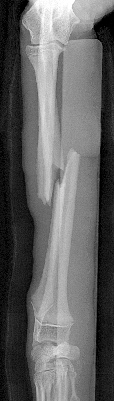

イタリアン・グレーハウンドの両前肢骨折

左前肢

左前肢は中和プレートのみなので2期癒合を目指します。

同じく術後19日目 左前肢

左前肢は2期癒合を目指すので、術後2,3週間前後のレントゲンでは

周囲に仮骨形成を認め、また、

骨折部の骨が溶けているように見えます。

これは骨再構築(骨芽細胞、破骨細胞、両方の活動によるもの)

されて起こる現象なので問題ありません。

インプラントの折損、明らかな動揺は認めません。